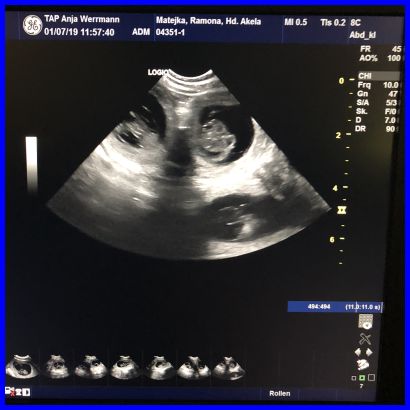

Da ist es, das erste Baby, man kann es ganz deutlich in der Fruchtblase sehen.

Hier auf diesem Bild kann man sogar drei Föten sehen.